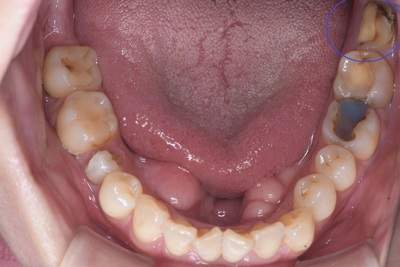

親知らずの抜歯症例

- 抜歯前の口腔内写真(下)

| 年齢 | 50代・女性 |

|---|---|

| 主訴 | 右上と左上下の親知らず |

| 親知らずの生え方 | 真っ直ぐに生えている |

| 抜歯時間 | 説明、麻酔含め各約30分 |

| 費用 | 各約1,240円(保険診療3割負担) (2024年12月現在) |

| 抜歯内容 | 抜歯後の負担を考慮して、右上、左上、左下の順で日にちを分けて抜歯しました。 |

| 治療方針 | 親知らずの手前の7番の虫歯治療が必要なため、先に虫歯になっている親知らずの抜歯から始めました。 |

| 担当者所見 | 左上親知らずは、メタルの被せ物が抜歯の際に外れ、中は虫歯で歯が溶けていました。 右上、左下もレジンのような材料で治療した痕がありましたが、いずれも大きく欠けており、歯として機能していませんでした。 |